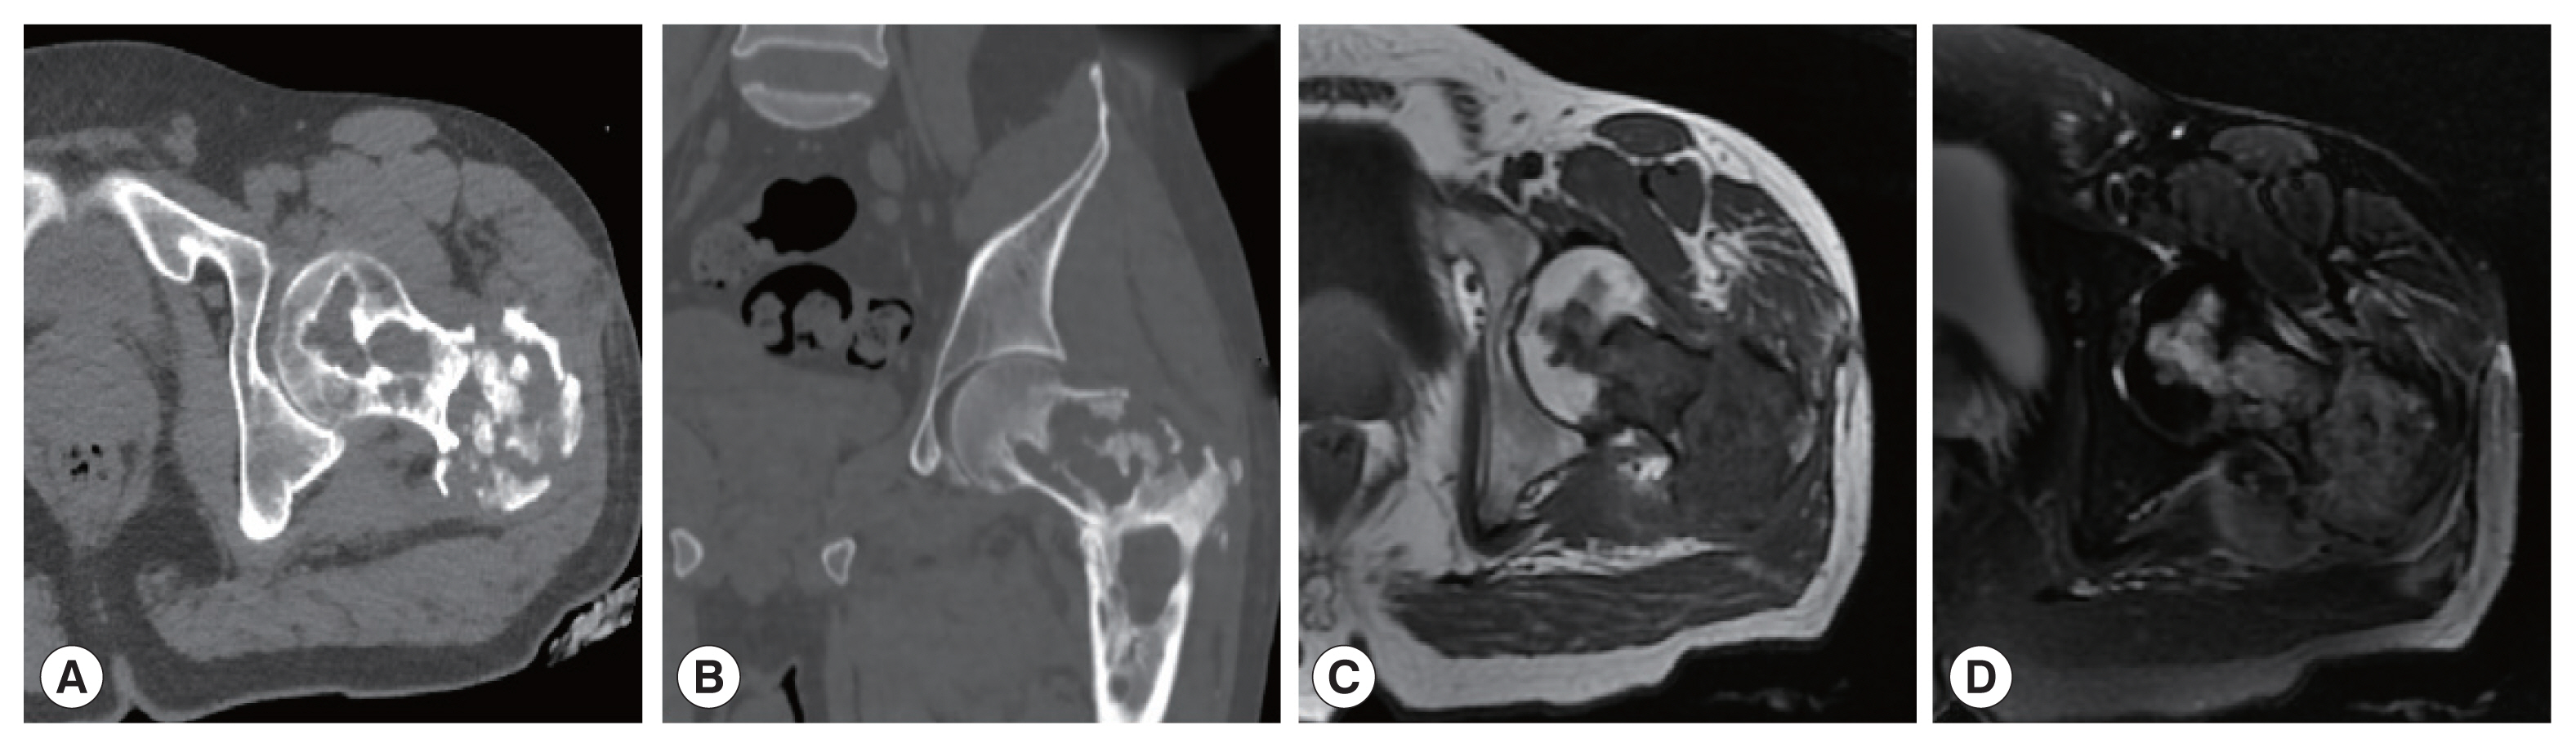

The CT images of patient 1 showed the uneven bone density and low-density bone destruction of the infected vertebral body. The boundary of the lesion was clear, but the edge was sclerotic. Multiple round low-density shadows and separation were seen, and the spinal canal was compressed and narrowed. The MRI scans also showed a low signal on T1WI, a high signal on T2WI, and a “grape bunch-like” cluster. The edge of the lesion was slightly enhanced on the enhanced scan, while no obvious enhancement was found in the interior portion. The lesion protruded into the spinal canal, causing spinal cord compression (Fig. 1). In patient 2, the lesion involving the left femoral head-femoral neck-femoral trochanter was seen on CT scan. The left femoral head, neck, and trochanter showed cystic expansive bone destruction, accompanied by sclerotic edge and dead bone formation. Local soft tissue masses were also recognized. The MRI showed an irregular low signal on T1WI, a high signal on T2WI, and a patchy high signal on T2WI in the vastus lateralis muscle (Fig. 2). Patient 3 showed osteolytic destruction of the vertebral body with wedge-shaped compression. The formation of sequestrum, intervertebral space stenosis, and swelling of the surrounding soft tissue were also noticed. In the other 3 patients (patients 4, 5, and 6), osteolytic destruction was observed, and some vertebral bodies showed wedge-shaped compression. Spinal canal stenosis and soft tissue masses were also seen locally.